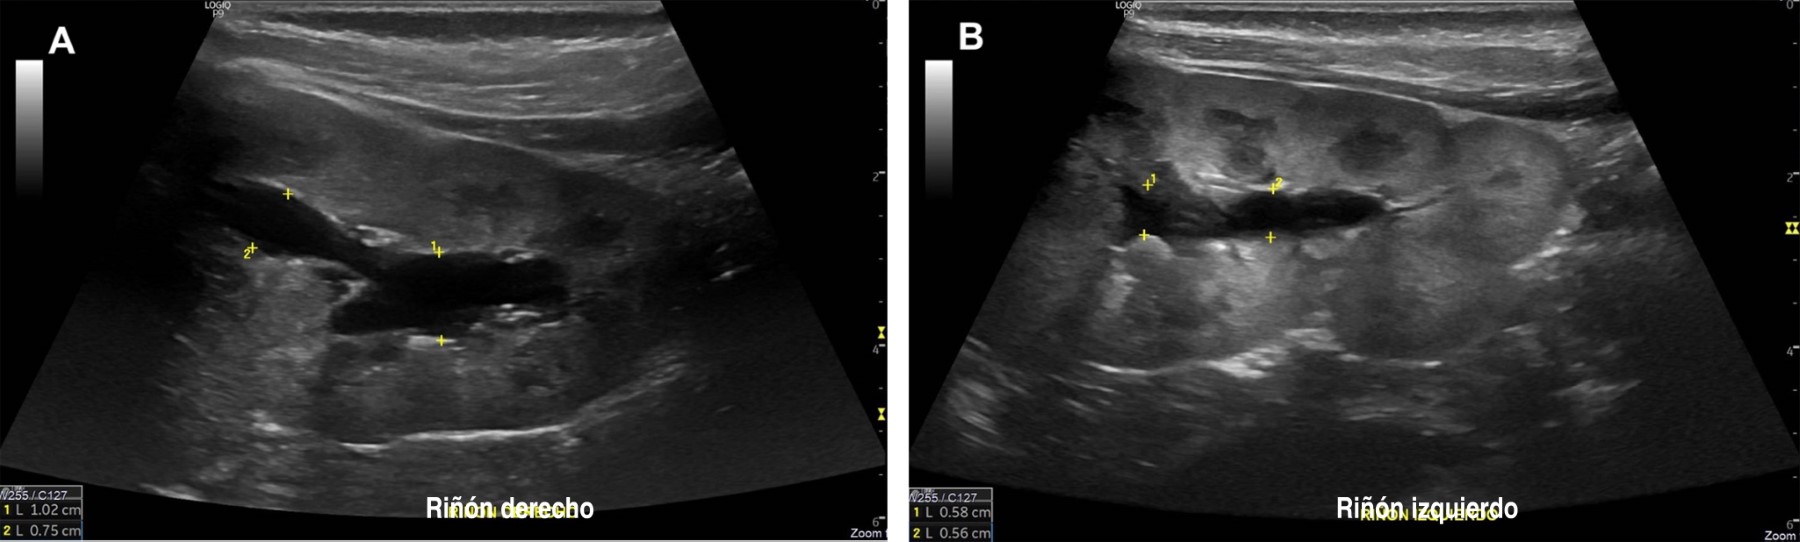

Con el enfoque de nefrología pediátrica el diagnóstico se orientó hacia una alteración tubular, incluyendo tubulopatía perdedora de sodio como el síndrome de Bartter. En este contexto, se solicitó la medición de aldosterona y actividad plasmática de renina, cuyos resultados fueron elevados. Los valores específicos de todos los estudios realizados, incluidos los cálculos correspondientes, se resumen en la Tabla 1. Como parte del abordaje, se realizó un ultrasonido renal que mostró, como único hallazgo, ectasia pielocalicial pasiva bilateral (Figura 1). Estas alteraciones, junto con las manifestaciones previamente mencionadas, fortalecieron la sospecha diagnóstica, por lo que se decidió iniciar tratamiento con aporte oral de potasio y sodio en forma de cloruro, indometacina y un inhibidor de bomba de protones (para proteger la mucosa gástrica).

El síndrome de Bartter es una enfermedad tubular renal autosómica recesiva causada por mutaciones en genes que codifican canales iónicos o transportadores en la rama ascendente gruesa del asa de Henle.7 El tipo III se caracteriza específicamente por mutaciones en el gen CLCNKB, localizado en el cromosoma 1p36, que afectan la reabsorción de cloruro en esta región del túbulo renal.17 Este gen codifica el canal ClC-Kb, y se han identificado al menos 26 mutaciones distintas asociadas con amplia variabilidad fenotípica, lo que contribuye a las diferentes presentaciones clínicas de esta condición.17 Además de las alteraciones bioquímicas características, como la hipokalemia y la alcalosis metabólica, este subtipo puede manifestarse con hipocalciuria o hipercalciuria, además de hipomagnesemia.6 En nuestro paciente, la calciuria era normal y se realizó un ultrasonido renal que no evidenció nefrocalcinosis; el único hallazgo fue ectasia pielocalicial pasiva secundaria a la poliuria crónica. La diversidad clínica complica el diagnóstico, ya que puede simular otras tubulopatías, como las formas neonatales del síndrome de Bartter o el síndrome de Gitelman.17 Respecto a este último, aunque ambos comparten hipokalemia y alcalosis metabólica, el síndrome de Gitelman se asocia típicamente con hipomagnesemia e hipocalciuria, con frecuencia asintomático o con síntomas leves, y por lo general de inicio más tardío.18 Por otro lado, la hipocloremia es un marcador distintivo del síndrome de Bartter, siendo más grave que en el síndrome de Gitelman, como lo describen Seys y colaboradores.18 Este hallazgo destaca la importancia de evaluar los niveles de cloro sérico, como se observó en este paciente con hipocloremia persistente.